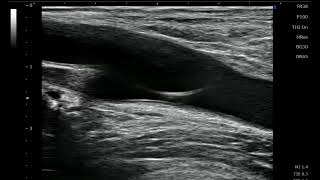

Ultrasound-guided tendon sheath release

OR00006 切らないばね指手術(超音波ガイド下腱鞘切開術)